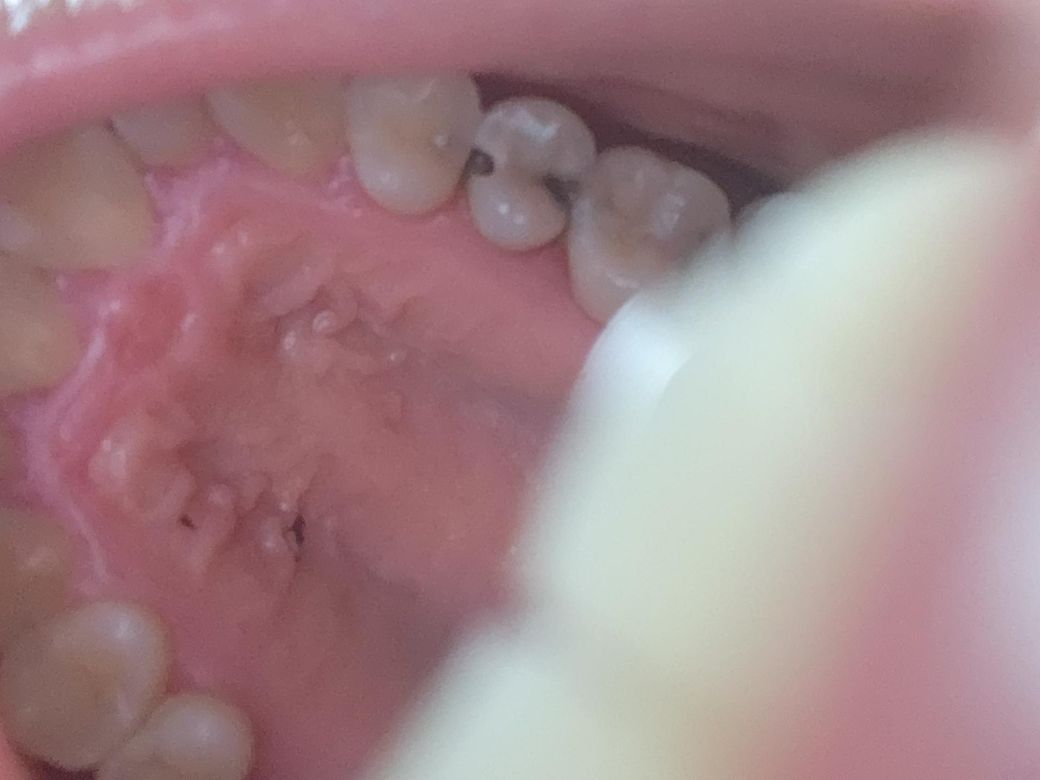

이빨이 아픈데 어디가아픈건지 모르겠는데요

저이빨이 아픈걸까요 음식씹으면 시큰거리는거외엔 불편한게 없어요 그리고 옆면으로 파여있는거같아요ㅜㅜ

사진이 흐리지만 양옆으로 파여있다면 충치가 꽤 진행된 상태일 것이라 치료 받으셔야 합니다.

사진으로 봤을 경우 인접면 충치가 매우 크게 진행된 것으로 보입니다. 충치를 제거하고 제거된 부위에 치과용 재료로 충전을 해야 하며 충치 제거하고난 뒤 신경이 노출이 된다면 신경치료가 필요할 수 있습니다.

사진상으론 충치가 있어 치아 옆면이 이미 파였습니다. 양쪽 치아도 영향을 받고 있을 확률이 높고요.

얼마나 충치가 깊은지에 따라 달라질 수는 있는데 비교적 비용이 적게 드는 치료 방향은 GI라는 보험되는 재료로 떼우는 겁니다.